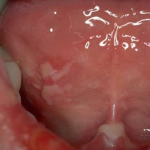

Pemphigis Vulgaris =الفقاع الشائع